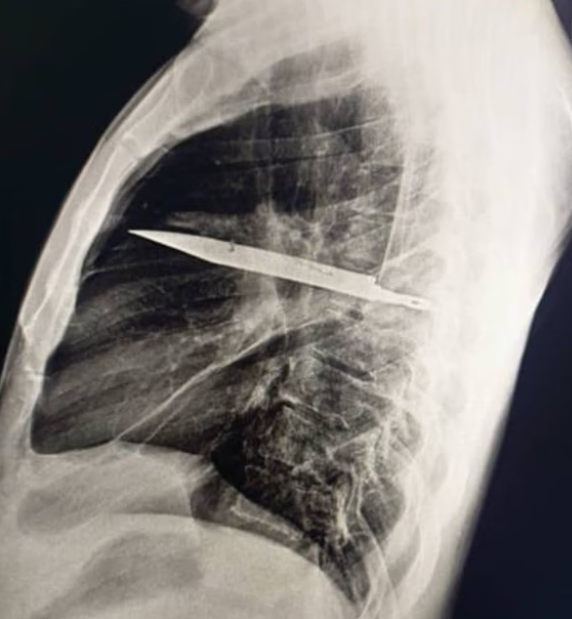

В Танзании врачи зафиксировали уникальный случай, когда 44-летний мужчина прожил восемь лет с лезвием ножа в грудной клетке, не подозревая об этом. Выявить посторонний предмет удалось только после того, как у него появились гнойные выделения из раны под правым соском.

Человек 8 лет прожил с ножом в груди. Фото из открытых источников

Проведенные рентген и компьютерная томография обнаружили, что крупное металлическое лезвие вошло через спину в районе правой лопатки, прошло между пятым и шестым ребрами и остановилось в передней части грудной клетки. Вокруг него образовались залеченные переломы и очаги гноя.